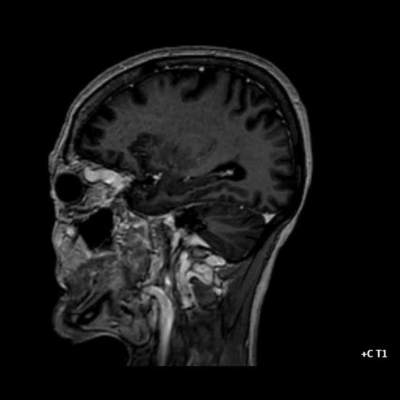

- A) Orbital MRG’de yağ baskılı T2A görüntülerde sol orbital globta ekzoftalmus (ok) izlenmiş olup retrobulbar yağlı dokuda kirlenmeler (ok) ve dilate superior oftalmik ven (ok) dikkati çekiyor. Beyin MRG’de kontrastlı T1A görüntüde sol kavernöz sinüste simetriğine oranla genişleme (ok) izleniyor.

- BT ve MRG: Propitozis, ekstraokuler kaslarda genişleme, superior oftalmik vende genişleme ve tortiyozite, ipsilateral kavernöz sinüste genişleme gösterilebilir. Serebral venöz konjesyonu olan ve intrakraniyal basınçları yükselen hastalarda serebral ödem, hemoraji, leptomeningeal ve kortikal venlerin dilastasyonunu görülebilir. Bunlara ek olarak travmaya sekonder olgularda BT ile eşlik eden fraktürler gösterilebilir.

- Olgumuzun DSA incelemelerinde sol ICA ve ECA’dan kavernöz sinüse fistülöz bağlantı olduğu izlenmiş ve coil embolizasyon işlemi uygulanarak tedavi edilmiştir.